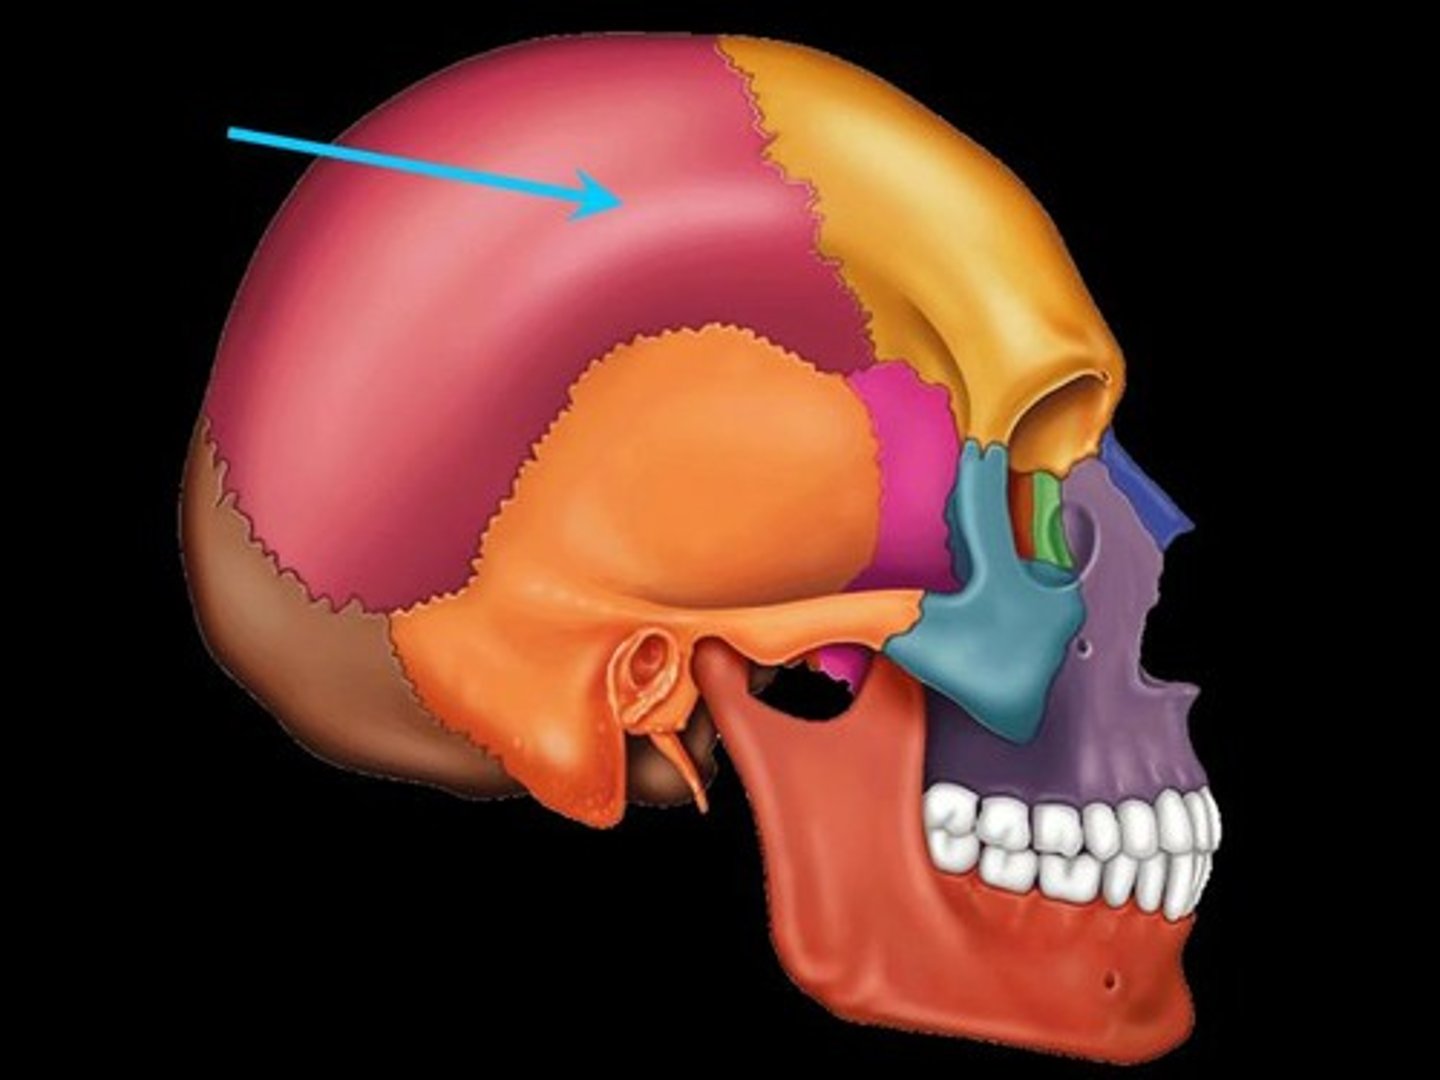

Parietal Bone

either of two skull bones between the frontal and occipital bones and forming the top and sides of the cranium